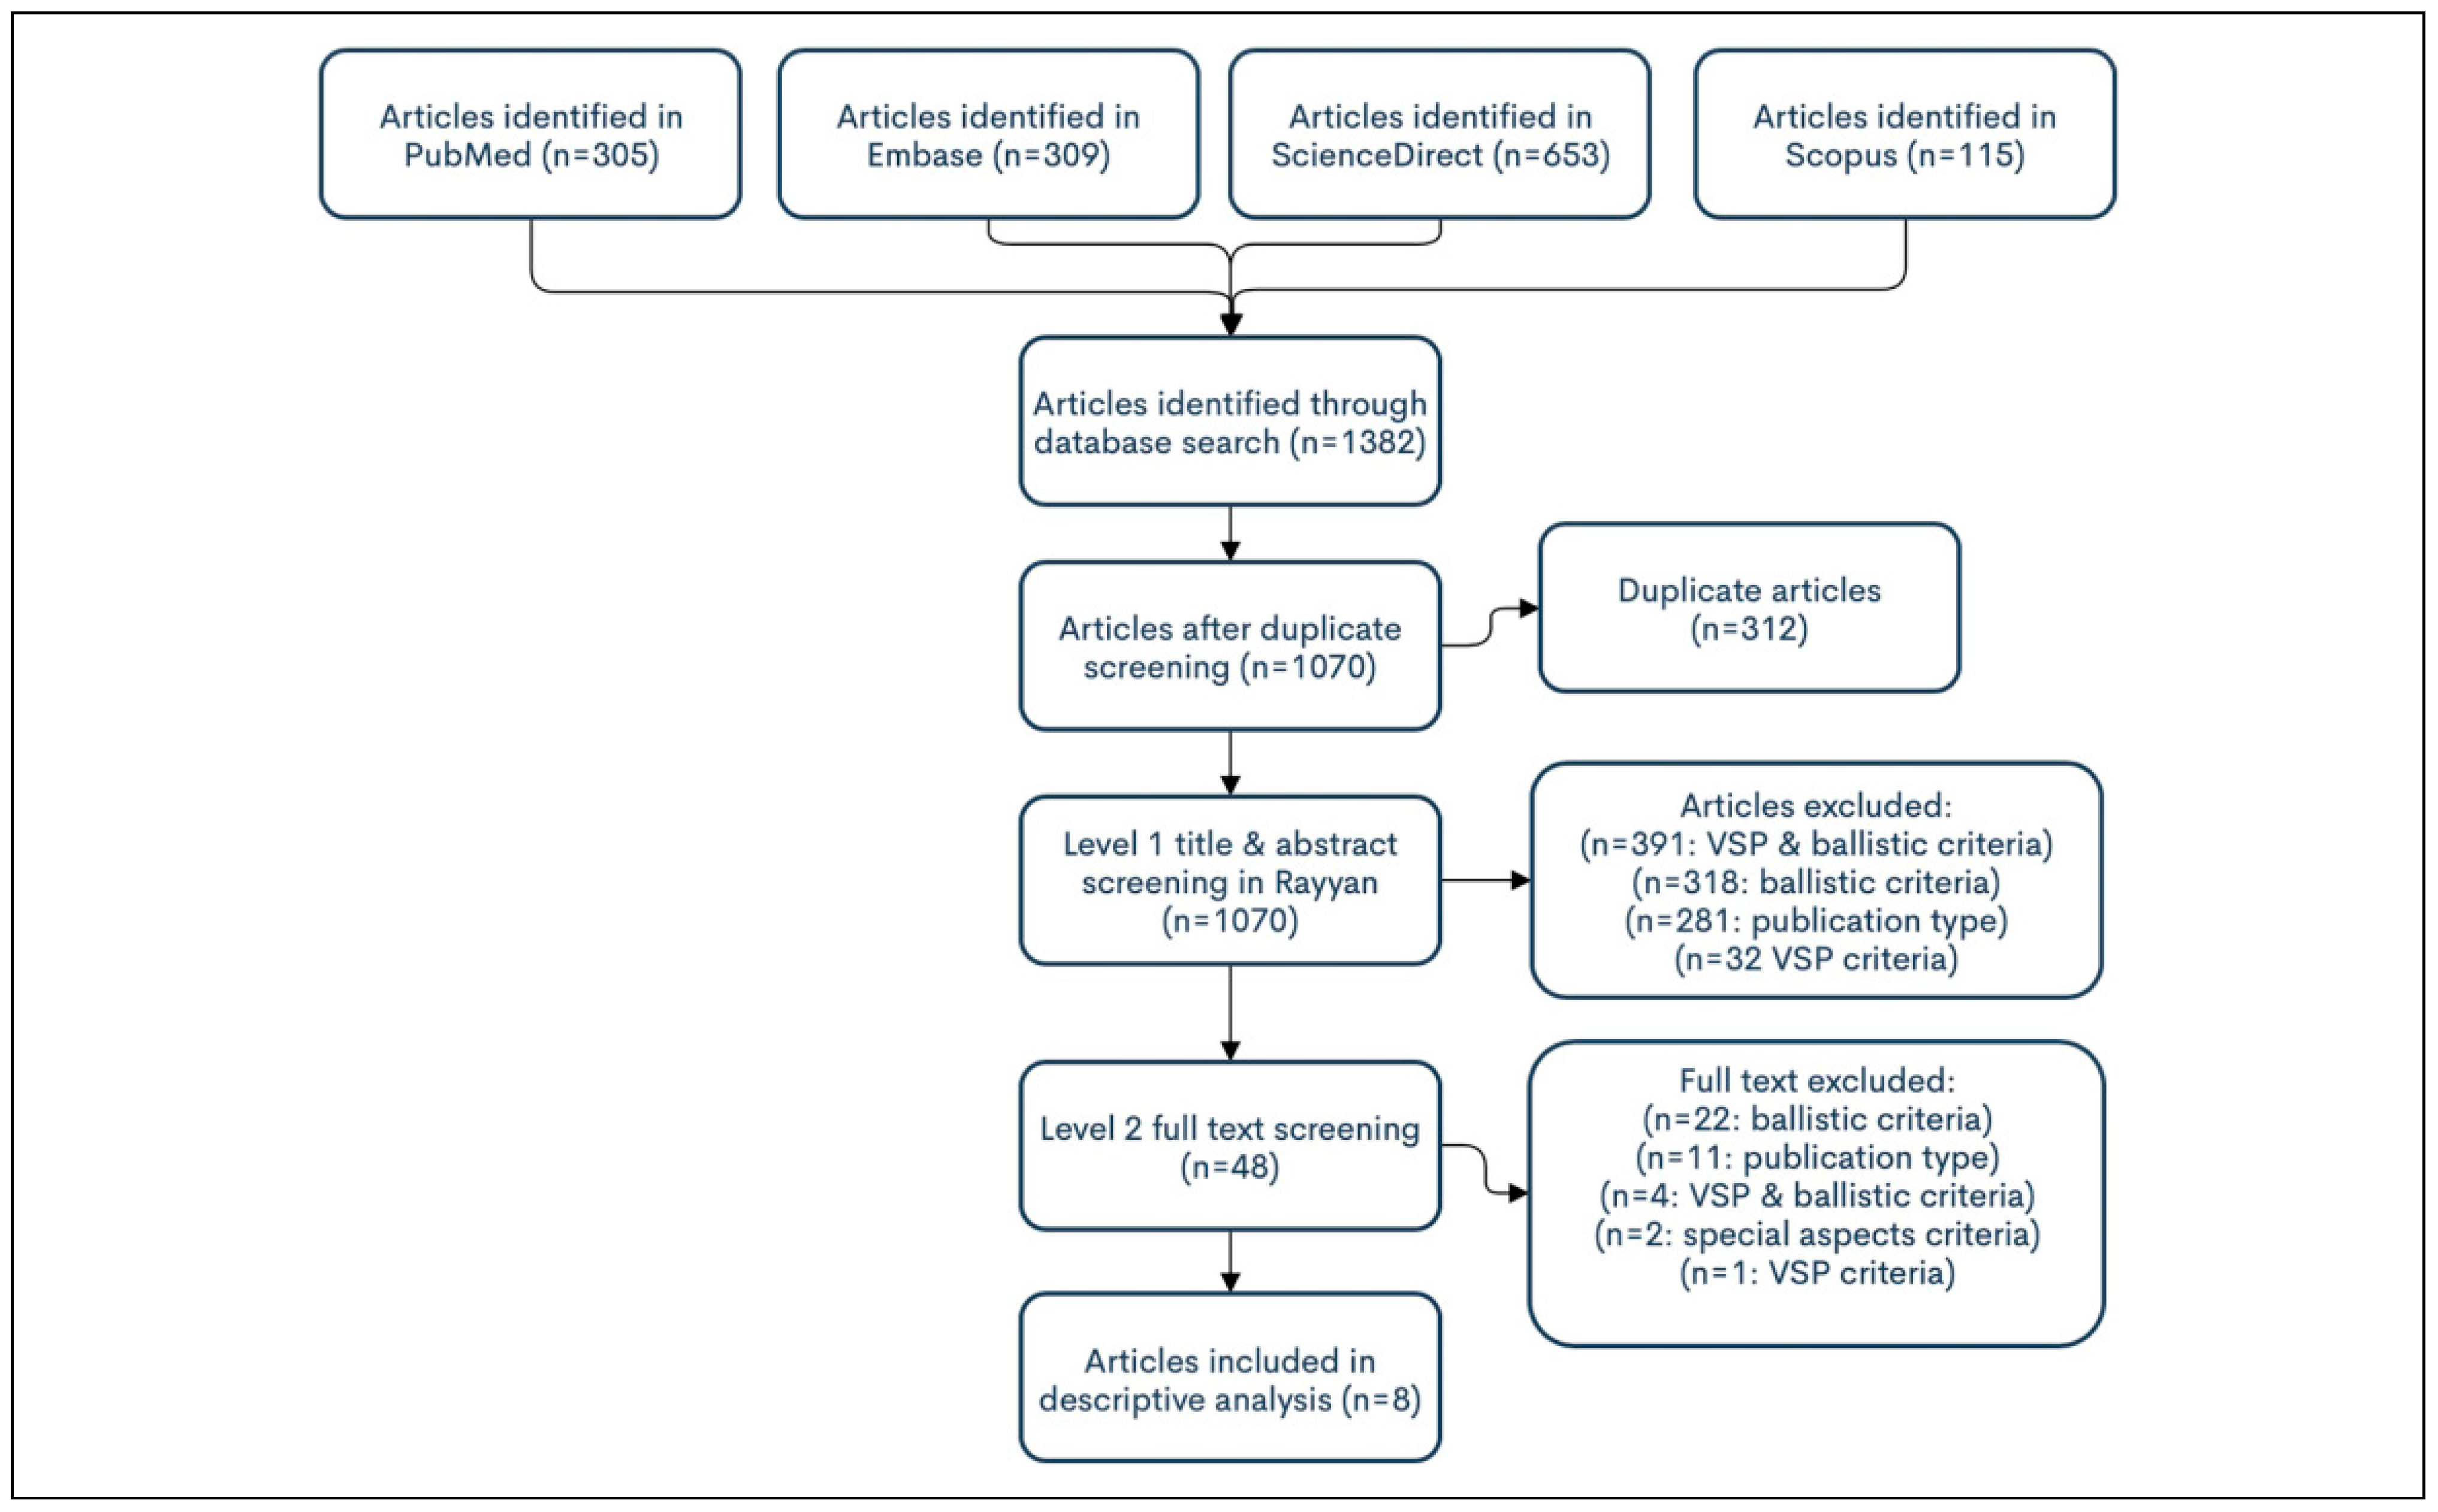

Materials and Methods

Systematic Review

Systematic Review